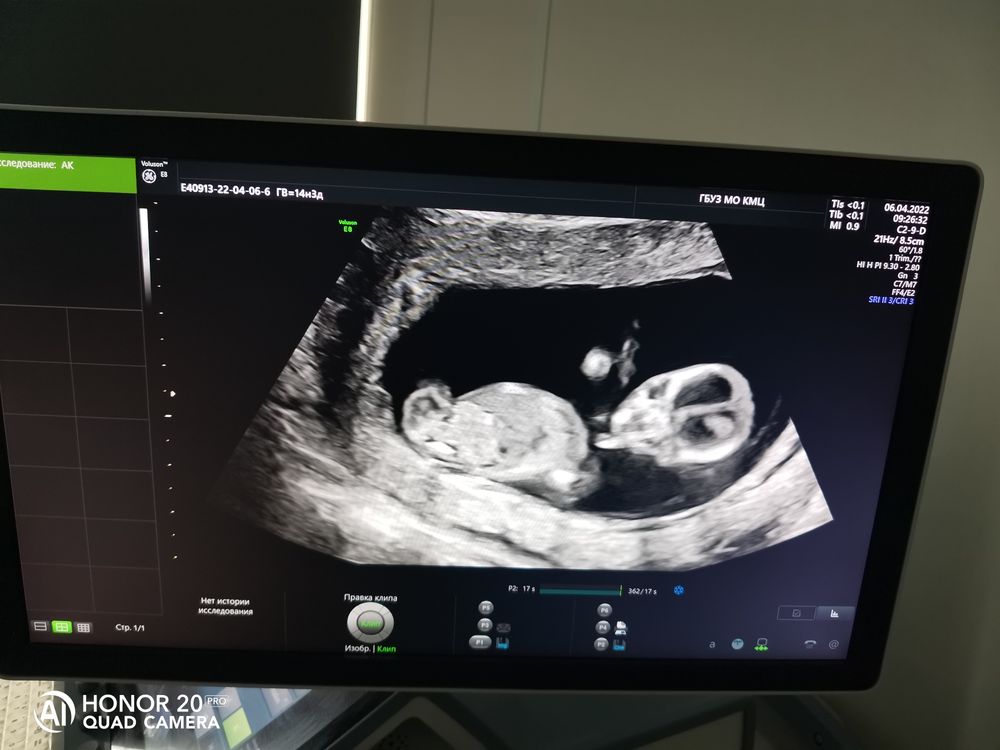

Вчера ходила на 1 скрининг. Всё хорошо, сказали рисков и патологий развития нет. Срок по-прежнему отстаёт от срока по месячным. Поставили срок 12,6.

Про пол ничего не сказали, а я постеснялась спрашивать.

Посмотрела на своего тигреночка, в этот раз не так активно махал ручками и ножками, спал, наверное)

Сердцебиение 159, прикрепление по задней стенке.